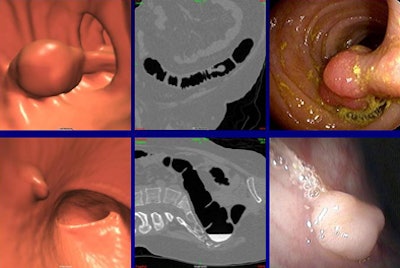

| Concordant findings included a 23-mm pedunculated lesion (top row), confidence level 3, that was seen on both 3D (upper left) and 2D (upper middle) views and confirmed at optical colonoscopy (upper right). Bottom row, a 6-mm sessile polyp (confidence level 3) was seen at both 3D (bottom left) and 2D (bottom middle) views and confirmed at colonoscopy (bottom right). All images courtesy of Dr. Steven Wise. |